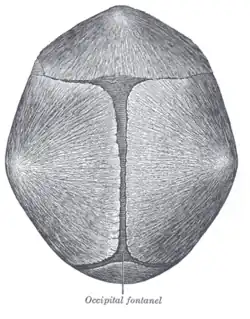

Observatory signs of trigonocephaly are:

- a triangular forehead seen from top view leading to a smaller anterior cranial fossa

- a visible and palpable midline ridge

- hypotelorism inducing ethmoidal hypoplasia